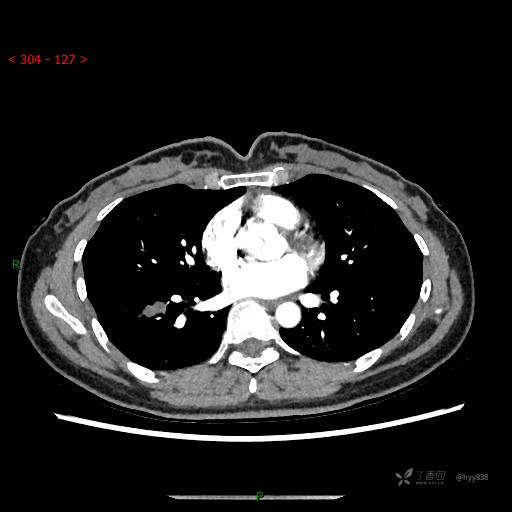

静脉期

CT值